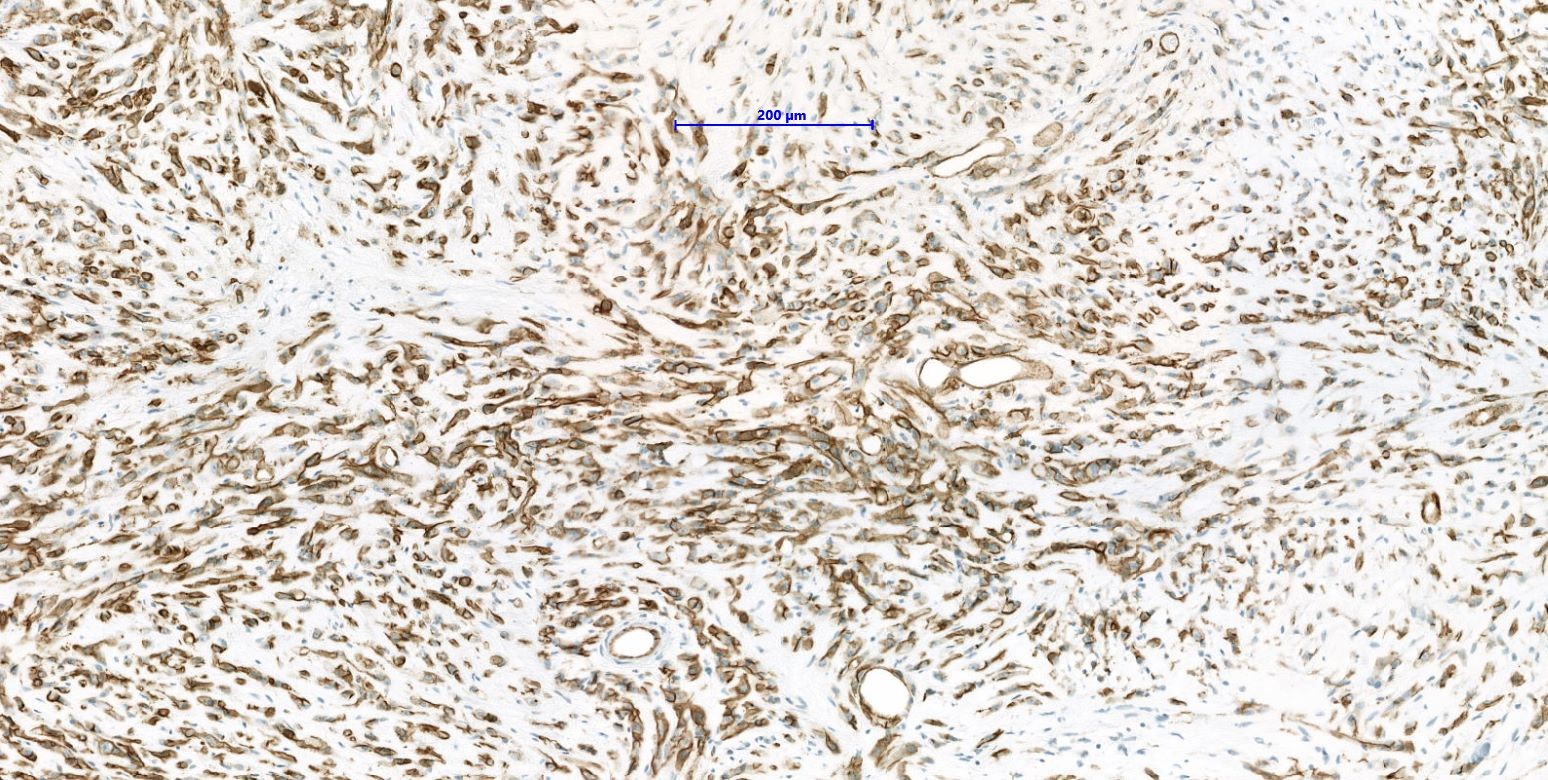

Microscopic (histologic) images

- WWTR1-CAMTA1 subtype (classic EHE):

- Cords, strands or small nests of large endothelial cells with abundant eosinophilic cytoplasm embedded in a myxohyaline stroma

- Tumor cells have vesicular, round to oval, sometimes indented nuclei

- Some tumor cells have intracytoplasmic, round, clear vacuoles representing small vascular lumina, which may contain erythrocytes

Positive stains

- ERG, CD31, CD34 (can be negative), podoplanin (D2-40), FLI1, von Willebrand factor (Diagn Pathol 2014;9:131, Am J Surg Pathol 1997;21:363)

- CAMTA1 in WWTR1-CAMTA1 rearranged tumors (Am J Surg Pathol 2016;40:94)

- TFE3 in YAP-TFE3 rearranged (less specific) (Genes Chromosomes Cancer 2013;52:775)

- Comment: Tumor is composed of cords and small nests of large endothelial cells with abundant eosinophilic cytoplasm embedded in a myxohyaline stroma. Immunohistochemically, the tumor cells are positive for ERG, CD31, CAMTA1, focally positive for keratin and are negative for CD34 and TFE3. The morphology and immunoprofile strongly support the diagnosis of WWTR1-CAMTA1 rearranged epithelioid hemangioendothelioma.